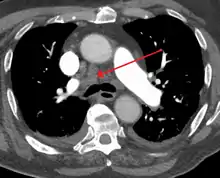

![]() 3D rendering of a high resolution computed tomography of the thorax, with mediastinum marked in blue. | |